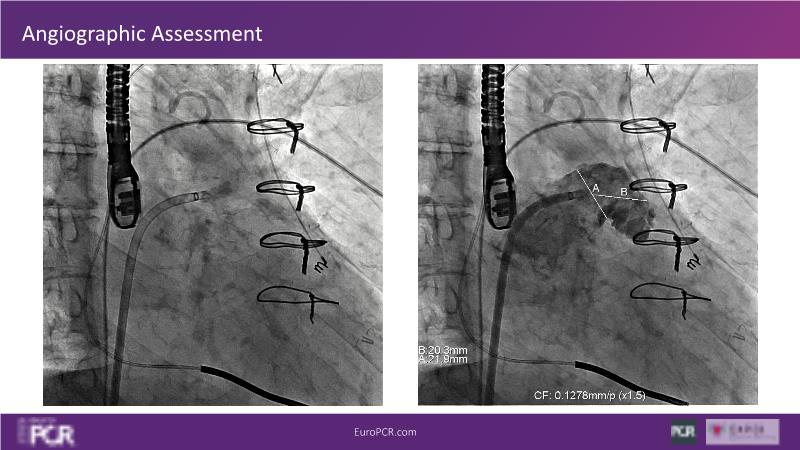

Explore this session to discover the latest innovations in interventional cardiology images, including the benefits of artificial intelligence and angio-CT in PCI/SHD procedures. Learn about Alphenix Evolve and the initial experiences with AI imaging in daily cathlab practice, alongside intraprocedural angio-CT guided LAAO, and engage in discussions on meaningful tools that can transform patient care.